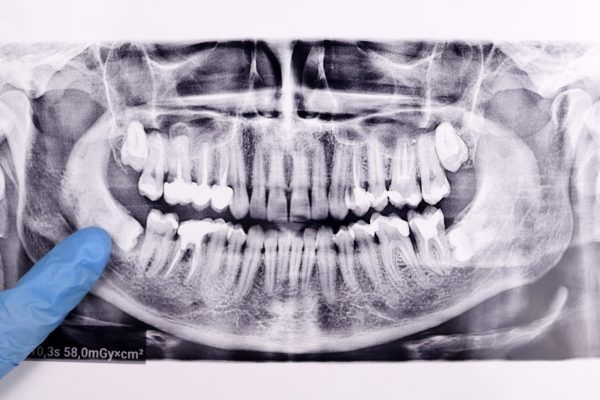

Dentist pointing out the wisdom teeth on an x-ray.

Your wisdom teeth, or third molars, are the last teeth to emerge from your gums during your late teens, or “age of wisdom,” which gives them their name. They often become impacted or trapped in the jaw bone and gums and fail to erupt as straight and fully functioning teeth. Impacted wisdom teeth nearly always have to be removed.

Why do we have wisdom teeth at all if they have to be removed so often? Human beings once had tougher diets. As our diets became softer and more refined, we no longer needed jaws for strenuous chewing. The jaws failed to develop, leaving little room for third molars. Today, most people experience at least one impacted wisdom tooth.